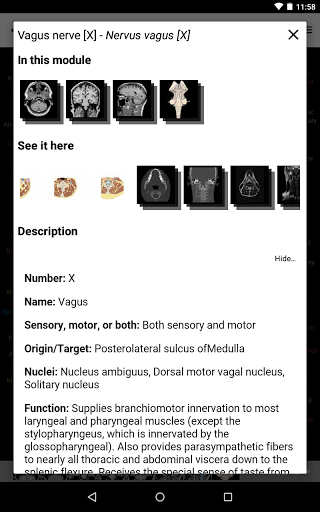

e-Anatomy tiene más de 26 000 imágenes que contienen series de imágenes en vistas axiales, coronales y sagitales, así como radiografías, angiografías, imágenes de disección, gráficos anatómicos e ilustraciones. Todas las imágenes médicas fueron etiquetadas cuidadosamente, más de 967 000 etiquetas disponibles en 12 idiomas, incluida la Terminologia Anatomica latina.

- Toque las etiquetas para mostrar las estructuras anatómicas

* Tablas introducidas en las definiciones de estructuras anatómicas para una mejor estructuración de datos

la vista de detalles de una estructura anatómica ahora se muestran los términos relacionados